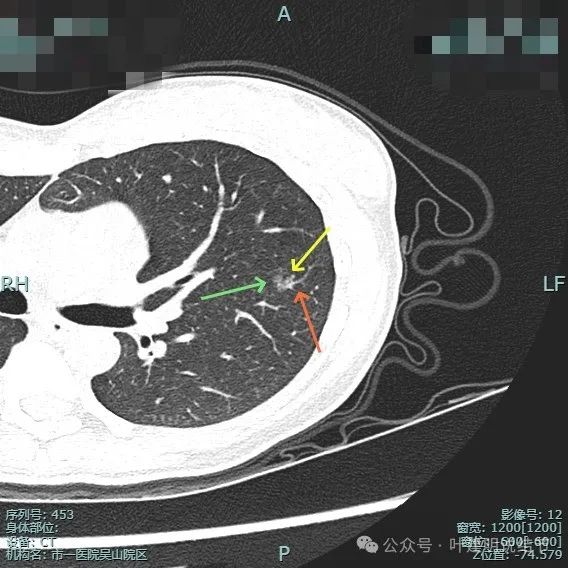

右侧病灶15:

病灶密度仍纯但不太均匀,整体轮廓与瘤肺边界清。

有小血管进入与类反晕征。

血管进入以及轮廓与边界清楚。

密度不均显杂乱。